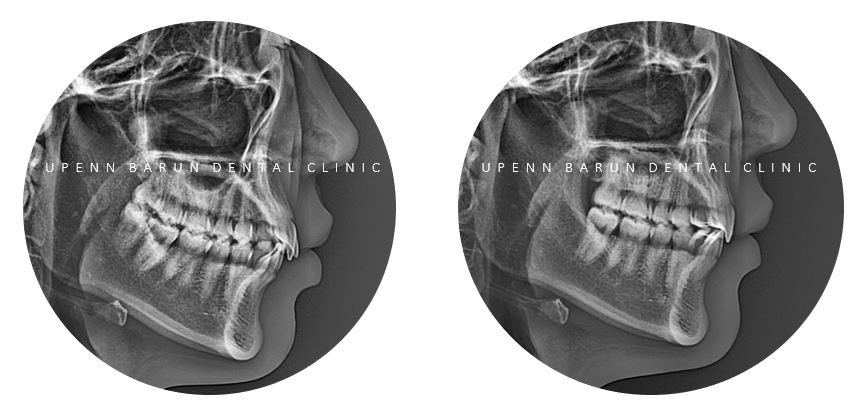

측면 사진을 보니 앞니가 튀어나와 뻐드러져 있고

인비절라인라이트 케이스 (Invisalign Lite Case)

첫번째 클린체크 (14개 장치)

첫번째 14개 장치의 교정기간 23/4~23/8 (5개월)

튀어나와 뻐드러져 있던 앞니의 각도가 개선이 되고

앞니들이 제 자리를 찾으며

삐뚤빼뚤했던 치아들이 올바르게 배열되었습니다.

두번째 클린체크 (14개 장치)

2nd clincheck

교정기간 23/4~24/3(11개월)

추가 14개의 장치를 통해

인비절라인교정치료가 잘 마무리 되었습니다 :)

돌출된 앞니는

넘어지거나 운동할때 외상을 입게 되면

소중한 치아가 부러지거나 손상될수 있으므로

교정을 통해 예방이 필요합니다 :)

인비절라인을 통해

앞니의 각도 개선 뿐만 아니라

과개교합이 해결되면서

치아의 심미적인 요소 뿐만 아니라

기능적인 요소 또한 개선시킬 수 있었어요. :)